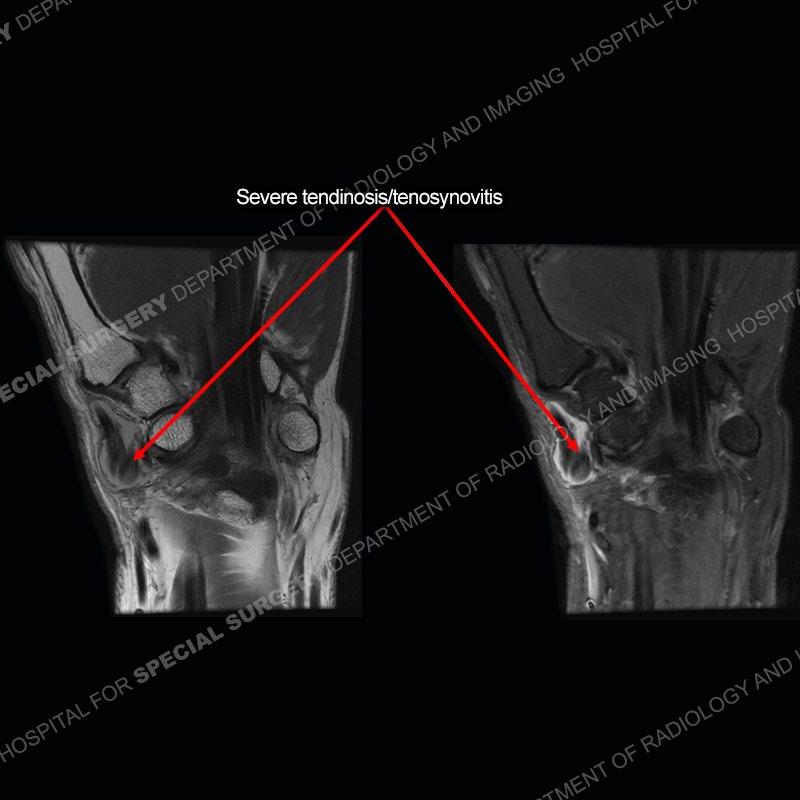

The radiographs in this case are not particularly contributory. The MRI demonstrates tenosynovitis of the first extensor compartment manifest by fluid/synovitis distention of the tendon sheaths. Multiple tendon slips are present of the abductor pollicis longus (APL) and with severe tendinosis seen of one of the tendon slips. Other areas of slightly increased signal and tendinosis are present of the components of the APL. Noted is a somewhat prominent septum separating the more dorsal extensor pollicis brevis (EPB) from the APL.

There can also be a partial or complete septum between the APL and EPB. This can particularly come into play with injections and positioning the needle into both sub-compartments to ensure that both tendons are bathed in the injectate.